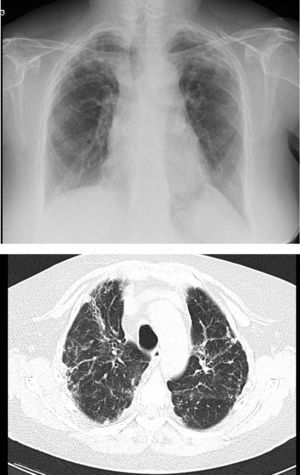

In unilateral transplant recipients, pulmonary function stabilises earlier, around the third month, because there is less trauma from the surgery. In these patients, maximum pulmonary function is lower than in bilateral transplant recipients and is also affected by the characteristics of the residual native lung. In recipients with interstitial disease, there is a tendency for the native lung to collapse, so the graft lung expands freely into the corresponding hemithorax (Fig. 1). There may be mild or moderate residual restriction and altered diffusion due to the presence of the native lung.8